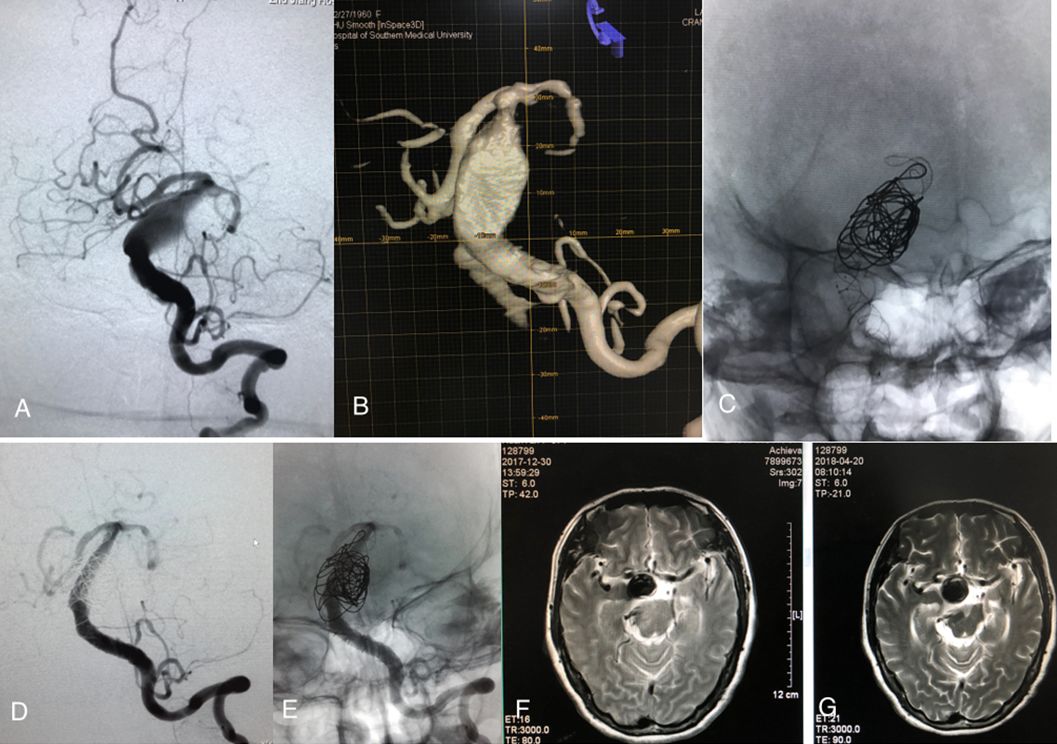

图1 57岁女性,以嗜睡、血压增高、四肢乏力发病。A, B. DSA示左椎动脉远端至基底动脉全程扩张延长,基底动脉全程呈梭形动脉瘤样改变; C. 2个LEO支架(5.5mm×75mm、5.5mm×50mm)及近端一枚Solitaire支架(6mm×30mm)覆盖左椎至基底动脉全程扩张延长处,并于基底动脉梭形动脉瘤样改变处植入少量弹簧圈; D,E. 3个多月后复查提示左椎至基底动脉延长扩张处修复良好;F,G. 治疗前与治疗后3个月的MR对比,重建血流的管腔外面的血栓没有明显变化